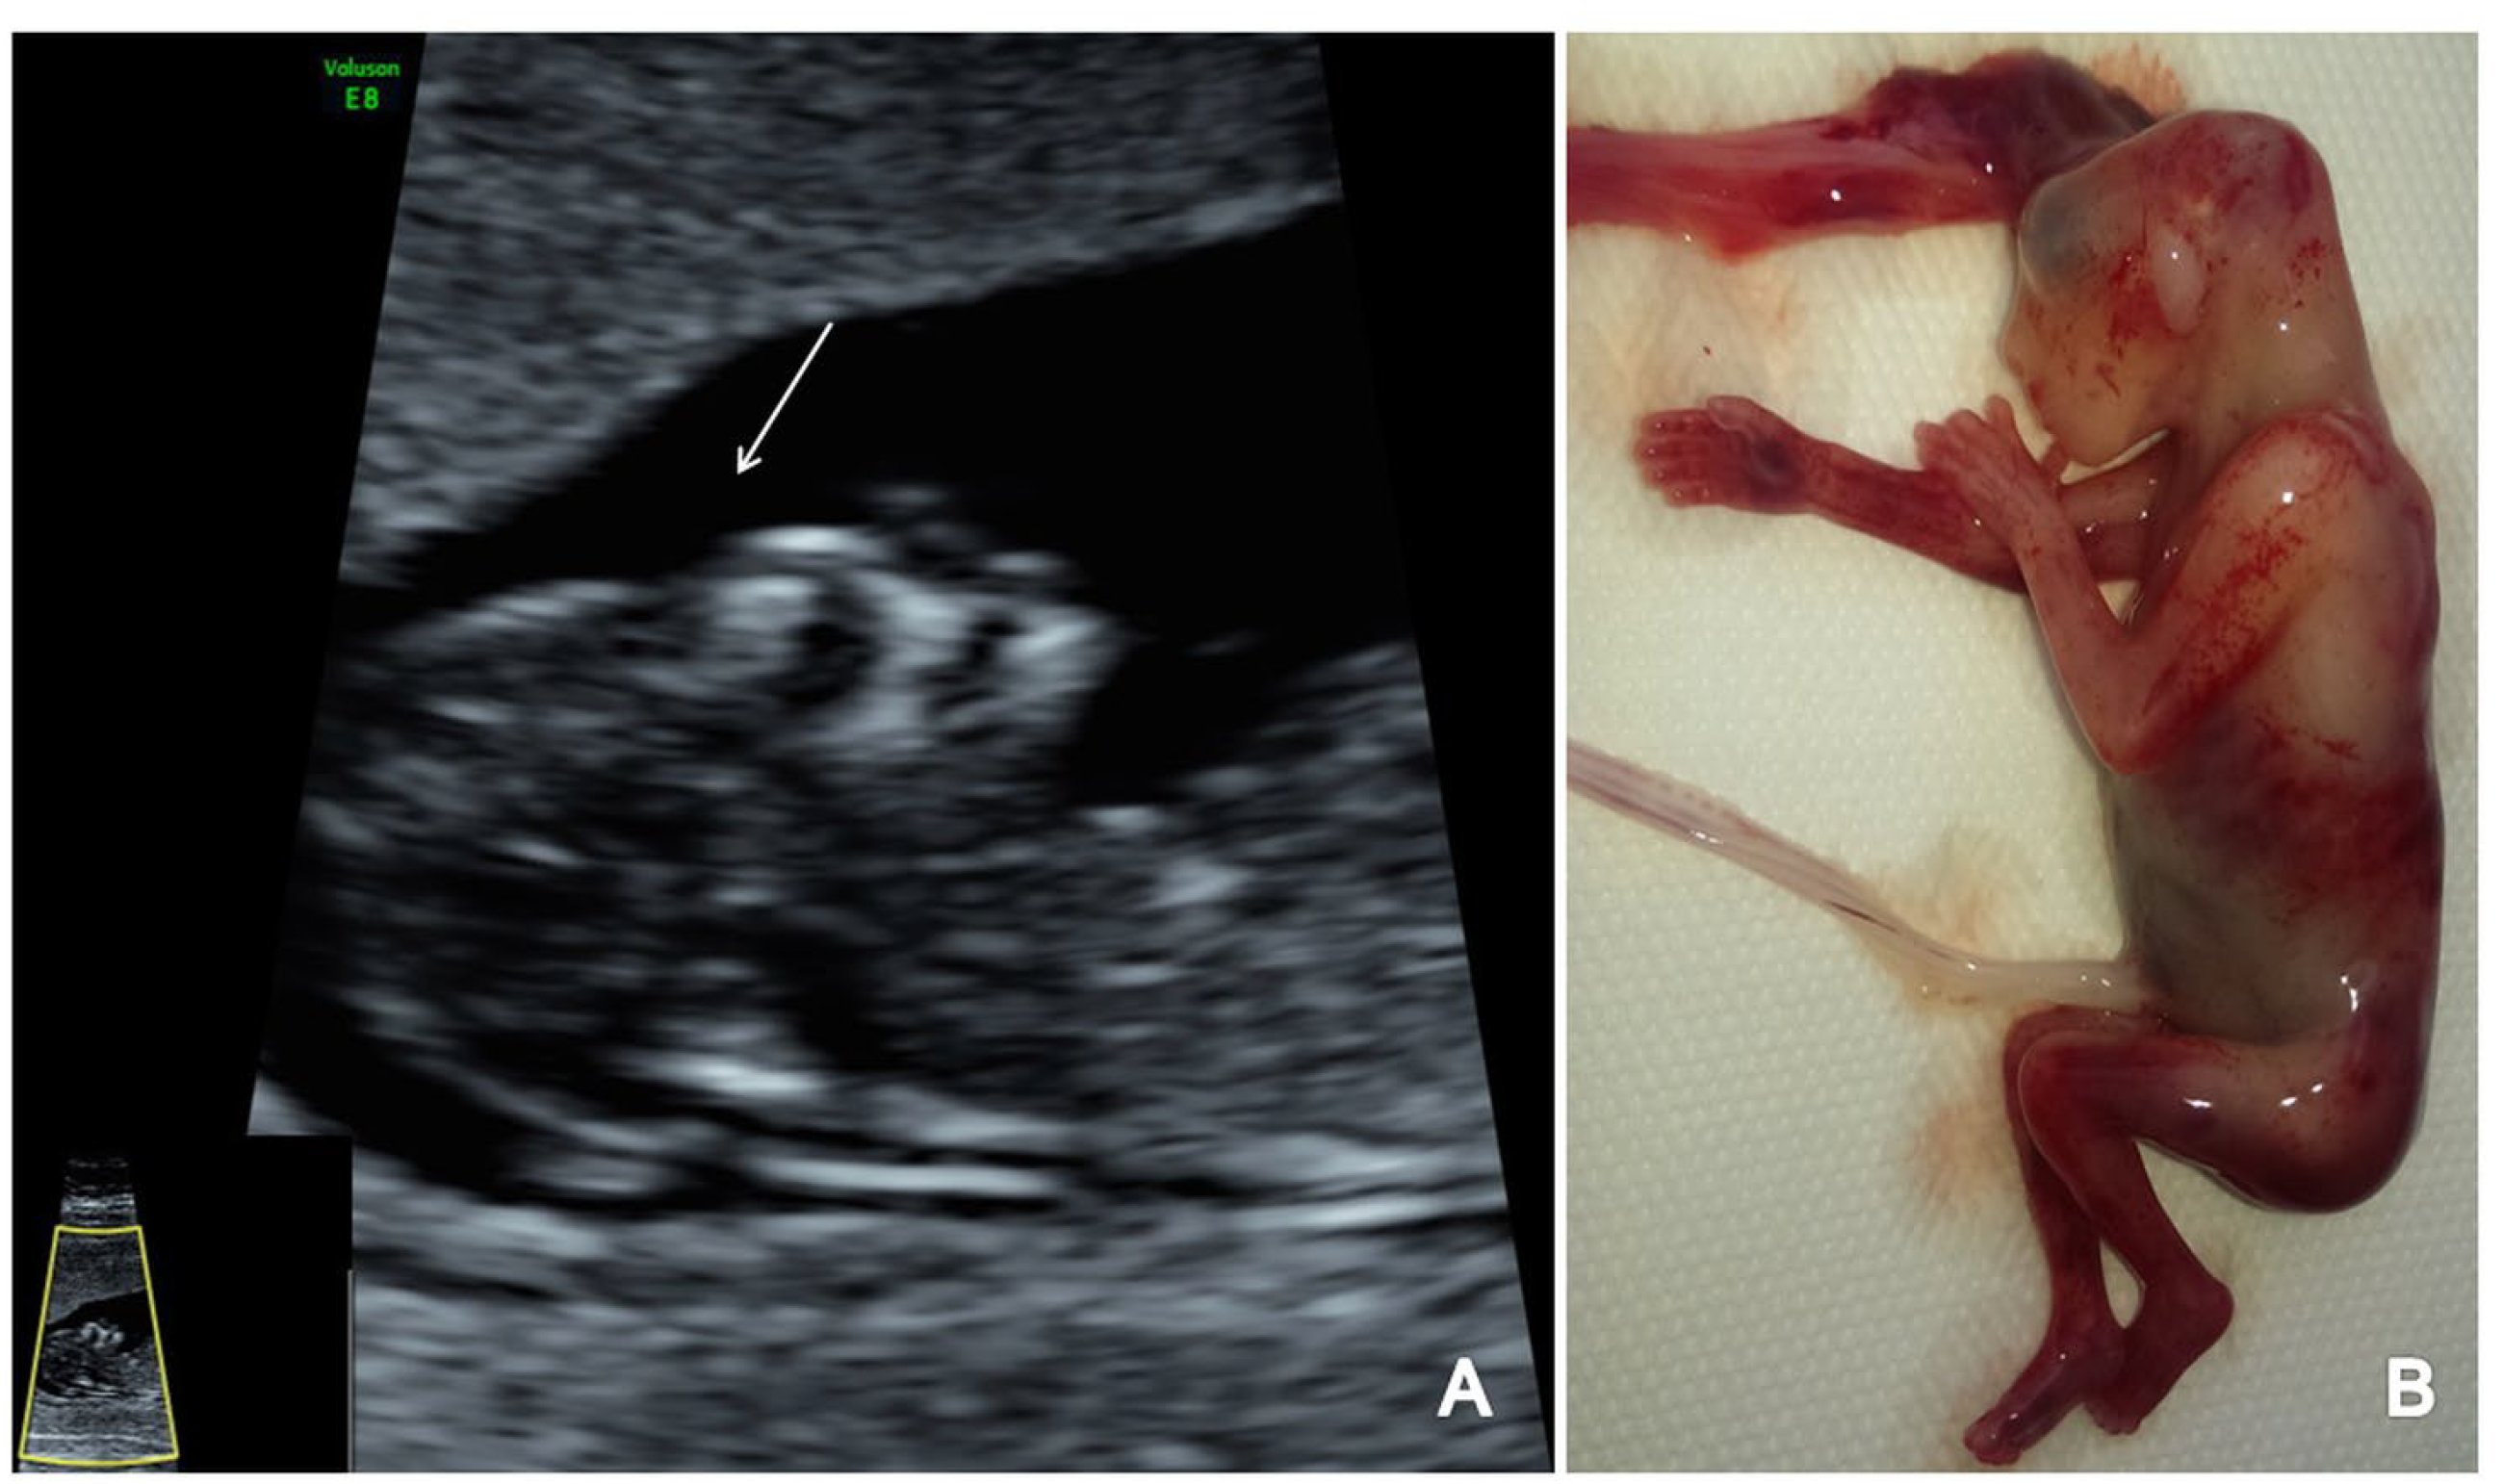

Figure 3.

A case of OSB diagnosed at 12 weeks + 3 days (Case 1): (A) transverse view of enlarged choroid plexus (the ‘dried up’ brain sign, arrow); (B) displacement of mesencephalon and aqueduct of Sylvius and deformation against occipital bone (‘the crash sign’, arrow); (C) mid-sagittal view of the fetal face showing the displacement of BS, which appears thicker (arrow) and with an increased BS/BSOB ratio; (D) sagittal view by transvaginal approach demonstrating the abnormal aspect of the spine—kyphoscoliosis (arrow); (E) specimen presentation of OSB after medical TOP.

Figure 4.

A case of OSB diagnosed at 13 weeks + 2 days (Case 3): (A) transverse view of the fetal head showing normal choroid plexus (arrow) and the filling of lateral cerebral ventricles; (B,C) further evaluation of the cerebral ventricular system, in transverse planes of the brain showing the aqueduct of Sylvius (B) and the third ventricle (C) indicated by arrows; (D) sagittal view by transvaginal approach demonstrating the defect (arrow); (E,F) specimen presentation after medical TOP.